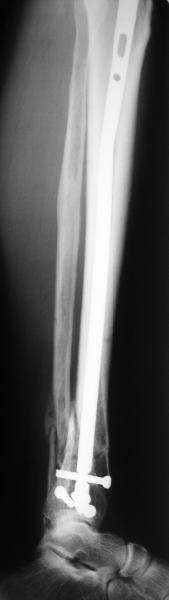

In delayed cases acute length restoration performed only in the tibia may leave the fibula shortened thus change the mortise. So it is reasonable to restore length of both bones simultaneously by distractor and fix the fibula not with open reduction and plating but just by a single perQ screw. Example attached.